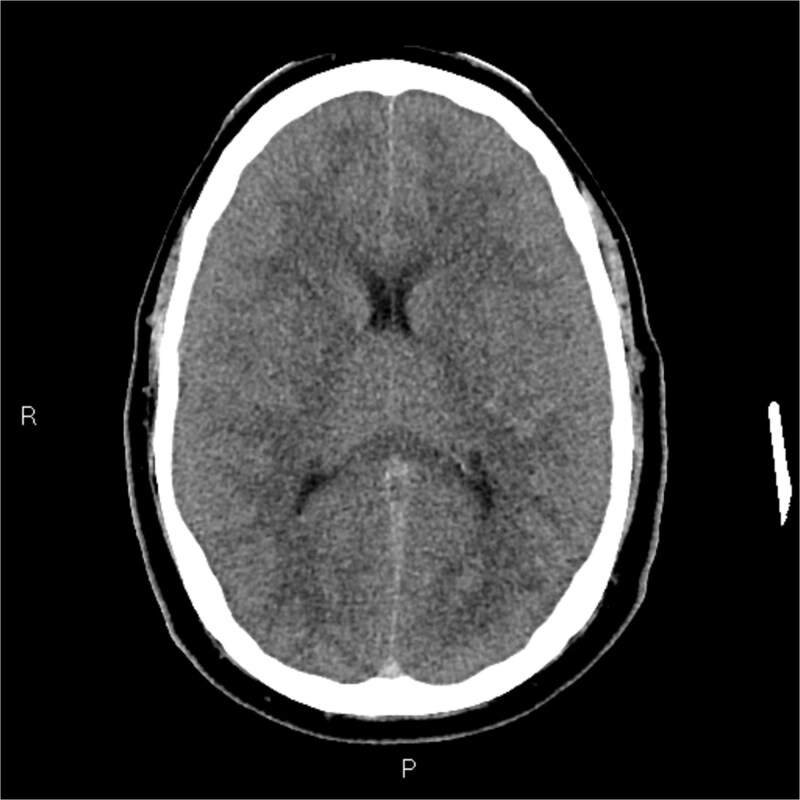

既往健康,免疫功能正常的中年男性,12小时右耳疼痛史,轻度流感样疾病后出院,到地区医院就诊。他的神经系统迅速恶化,瞳孔扩大,癫痫发作,需要插管。在紧急转至第四重症监护室后,多学科评估(耳鼻喉科和神经外科)、神经影像学和右耳鼓膜切开术证实耳瘤乳突炎合并脑静脉窦血栓形成。CT静脉造影显示广泛血栓形成,包括右乙状窦、横窦和上矢状窦。鼓膜切开术显示培养阴性血染脓。肺部微生物学结果对乙型流感和烟曲霉复合体呈阳性。尽管进行了最大限度的医疗治疗,患者还是出现了双侧静脉梗死、脑水肿和小脑扁桃体突出,并在48小时内进展为脑死亡。器官捐赠按照患者先前的意愿进行。即使在健康个体中,耳乳突炎也可引起快速、致命的颅内并发症,因此需要早期影像学检查、专家介入和警惕神经功能衰退。

A previously healthy, middle-aged immunocompetent man presented to a regional hospital with a 12-h history of right ear pain and discharge following a mild flu-like illness. He rapidly deteriorated neurologically, developing dilated pupils and seizures requiring intubation. Following urgent transfer to a quaternary ICU, multidisciplinary assessment (ENT and Neurosurgery), neuroimaging, and right ear myringotomy confirmed Otomastoiditis with catastrophic cerebral venous sinus thrombosis. CT venography demonstrated extensive thrombosis involving the right sigmoid, transverse, and superior sagittal sinuses. Myringotomy revealed culture-negative blood-stained pus. Pulmonary microbiology results were positive for Influenzae B and the Aspergillus fumigatus complex. Despite maximal medical management, the patient developed bilateral venous infarctions, cerebral edema, and cerebellar tonsillar herniation, progressing to brain death within 48 h. Organ donation proceeded in accordance with his prior wishes. Otomastoiditis can cause rapid, fatal intracranial complications even in healthy individuals, highlighting the need for early imaging, specialist input, and vigilance for neurological decline.